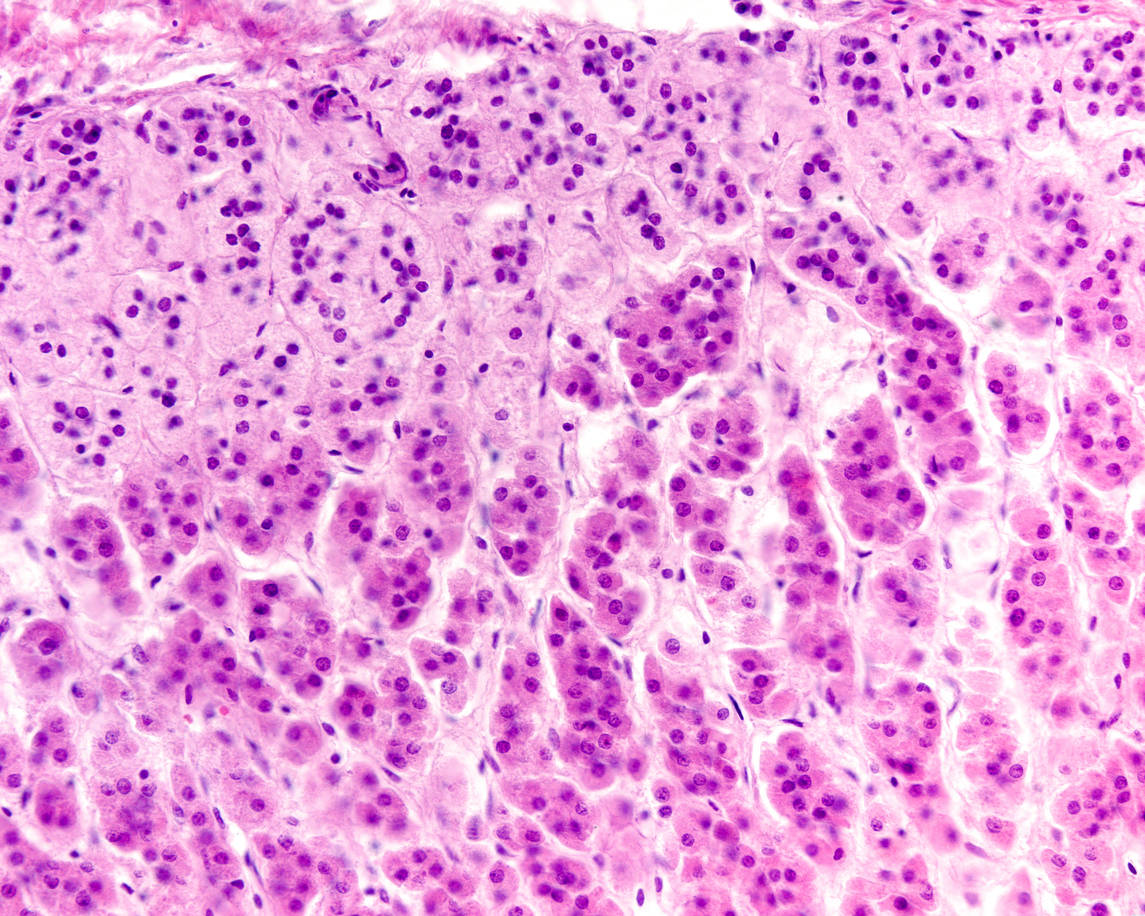

Comment se forment les plis de lʹintestin ou les alvéoles des poumons?

Des chercheurs du Swiss national centre of competence in research (NCCR) tentent de répondre à ce type de questions en appliquant les lois de la physique au vivant.

Des tornades de cellules sculptent nos organes (Unige)